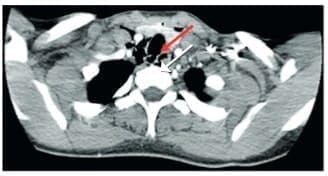

Se realizó un angiotac cervical con contraste endovenoso, encontrando enfisema subcutáneo en los tejidos blandos, con solución de continuidad (figura 4) y una lesión en el tercio medio de la tráquea, con compromiso de su pared lateral derecha (figura 5), sin poder descartar una lesión del esófago en su segmento cervical. No se observó compromiso vascular ni óseo.

Figura 4. Se observa enfisema subcutáneo con solución de continuidad en los tejidos blandos de la región cervical (flecha). Fuente: los autores.

Figura 5. Se observa lesión de la tráquea en el tercio medio que compromete su pared lateral derecha con solución de continuidad y enfisema subcutáneo (flecha). Fuente: los autores.